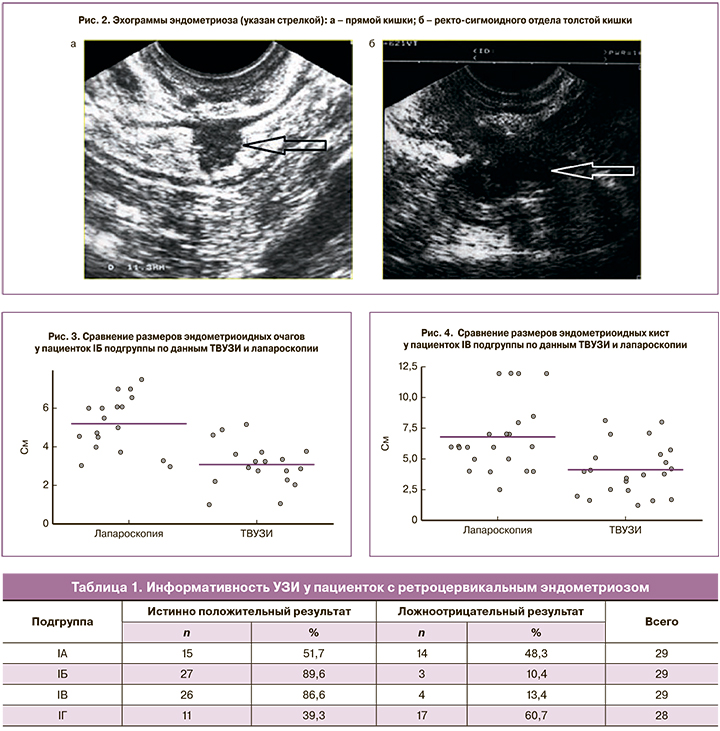

При распространении эндометриоидного инфильтрата на стенку кишки эндометриоз определялся в виде эхонегативной зоны овальной формы диаметром от 0,5до 3,0 см и протяженностью от 0,6 см до 3,0 см (рис. 2, а, б).

У пациенток IБ подгруппы средний диаметр эндометриоидного инфильтрата по данным ТВУЗИ составил 3,0 см, по данным лапароскопии – 5,1 см, результаты представлены на рис. 3 (p=0,001).

Как представлено на рис. 4, при сравнении результатов ТВУЗИ и лапароскопии средний диаметр эндометриоидных кист составил 4,1 см, по данным лапароскопии – 6,8 см (p=0,001).

Результаты ТВУЗИ по всем (IA–IГ) подгруппам представлены в табл. 1.

Анализ информативности УЗИ при спайках органов брюшной полости у пациенток с РЦЭ представлен в табл. 2.